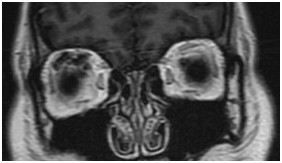

眼眶(病例-眼上静脉扩张)